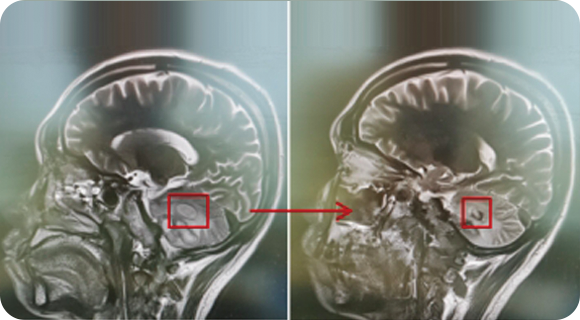

从事神经外科工作30年,擅长脑与脊髓血管类疾病、肿瘤、外伤等疾病的诊断与治疗,尤其擅长神经介入治疗各类脑血管疾病。累计完成介入栓塞颅内动脉瘤2000多例,颅内血管畸形数百例,夹闭颅内动脉瘤数百例,手术颅内与脊髓肿瘤数百例。在脑和脊髓血管病、肿瘤、外伤等方面有丰富的经验和较深造诣。

精通颅内动脉瘤介入栓塞和手术夹闭双技术,系统掌握脑动静脉畸形、颈内动脉海绵窦漏、硬脑膜动静脉漏等颅内血管疾病的诊疗和手术,精通颈动脉、椎动脉狭窄的血管内重建技术,以及颈动脉狭窄的内膜剥脱手术技术。在颅内肿瘤、椎管内肿瘤、颅脑损伤、高血压脑出血等疾病的诊治和手术,脑功能性疾病立体定向手术治疗等方面也积累了丰富的经验。